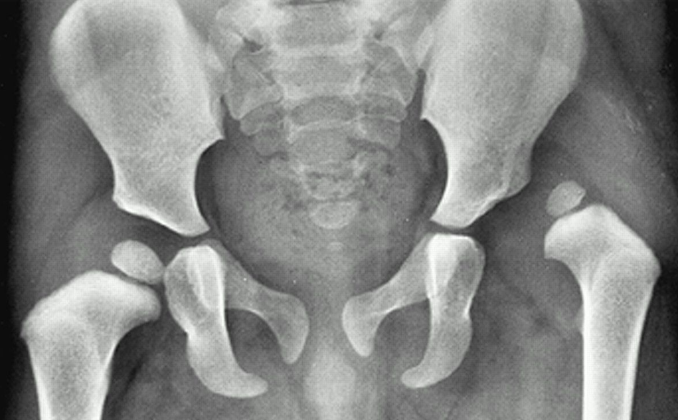

Hip dysplasia is a condition where the hip joint has not developed with normal alignment or coverage. Instead of the hip socket (acetabulum) fully supporting the ball of the thigh bone (femoral head), the socket may be shallow or angled differently. Over time, this altered joint structure can place increased stress on the cartilage and surrounding soft tissues.

- X-rays to assess hip socket depth, joint alignment, and signs of arthritis